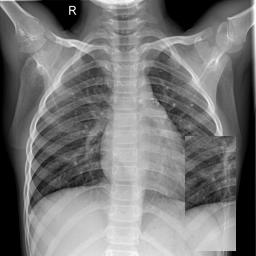

Large numbers of labeled medical images are essential for the accurate detection of anomalies, but manual annotation is labor-intensive and time-consuming. Self-supervised learning (SSL) is a training method to learn data-specific features without manual annotation. Several SSL-based models have been employed in medical image anomaly detection. These SSL methods effectively learn representations in several field-specific images, such as natural and industrial product images. However, owing to the requirement of medical expertise, typical SSL-based models are inefficient in medical image anomaly detection. We present an SSL-based model that enables anatomical structure-based unsupervised anomaly detection (UAD). The model employs the anatomy-aware pasting (AnatPaste) augmentation tool. AnatPaste employs a threshold-based lung segmentation pretext task to create anomalies in normal chest radiographs, which are used for model pretraining. These anomalies are similar to real anomalies and help the model recognize them. We evaluate our model on three opensource chest radiograph datasets. Our model exhibit area under curves (AUC) of 92.1%, 78.7%, and 81.9%, which are the highest among existing UAD models. This is the first SSL model to employ anatomical information as a pretext task. AnatPaste can be applied in various deep learning models and downstream tasks. It can be employed for other modalities by fixing appropriate segmentation. Our code is publicly available at: https://github.com/jun-sato/AnatPaste.

翻译:大量贴有标签的医学图像对于准确检测异常现象至关重要,但人工注解是劳动密集型和耗费时间的。自监学习(SSL)是一种培训方法,用于在不人工注解的情况下学习特定数据特征。一些基于SSL的模型被用于医学图像异常现象的检测。这些SSL方法有效地学习了多个特定领域图像的表解,如自然和工业产品图像。然而,由于医学专业知识的要求,基于SSL的典型模型在医学图像异常现象检测方面效率低下。我们展示了一个基于SSL的模型,可以进行基于解剖结构的、不受监督的异常现象检测(UAAD)。该模型使用解剖-觉粘贴(AnatPaste)增强工具。基于SSL的几种模型用于医学图像异常现象。这些异常现象与真正的异常相似,有助于模型识别这些异常现象。我们在三种开源的胸腔辐射数据集中可以使用模型,在基于解剖面结构结构的曲线下(AUSC),在92.1号中使用解析(Anal-SL)粘度图解为最高格式。